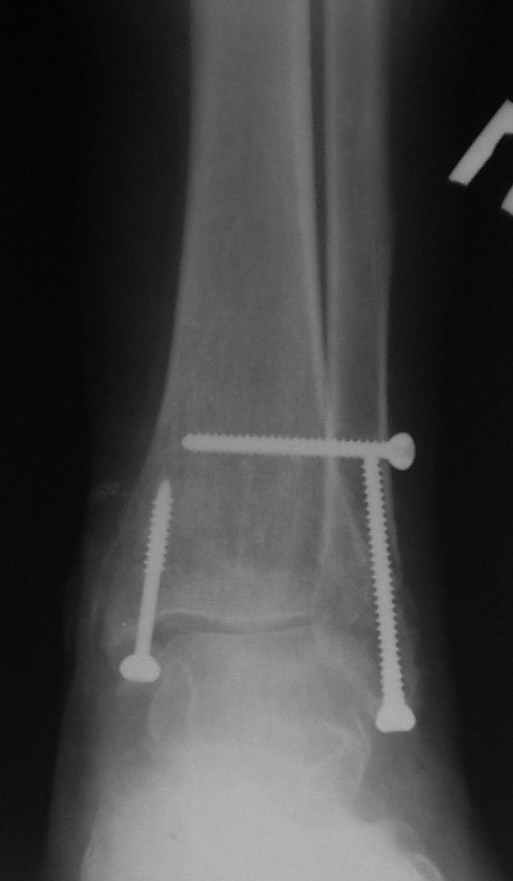

До операции 28 июля

Операция 29 июля